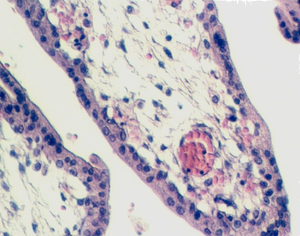

Look at the epithelium of the villi. The cytotrophoblast has disappeared and there is now one layer of syncytiotrophoblast. In places, the cytoplasm has thinned and the nuclei have accumulated in groups and clusters. These are called SYNCYTIAL KNOTS. Some of the villi show acellular pink-staining material called FIBRINOID which covers the surface. The accumulation is significant because it reduces maternal-fetal exchange.

Also, in mature placental villi are many more capillaries that lie closer to the surface. The following photographs show examples.